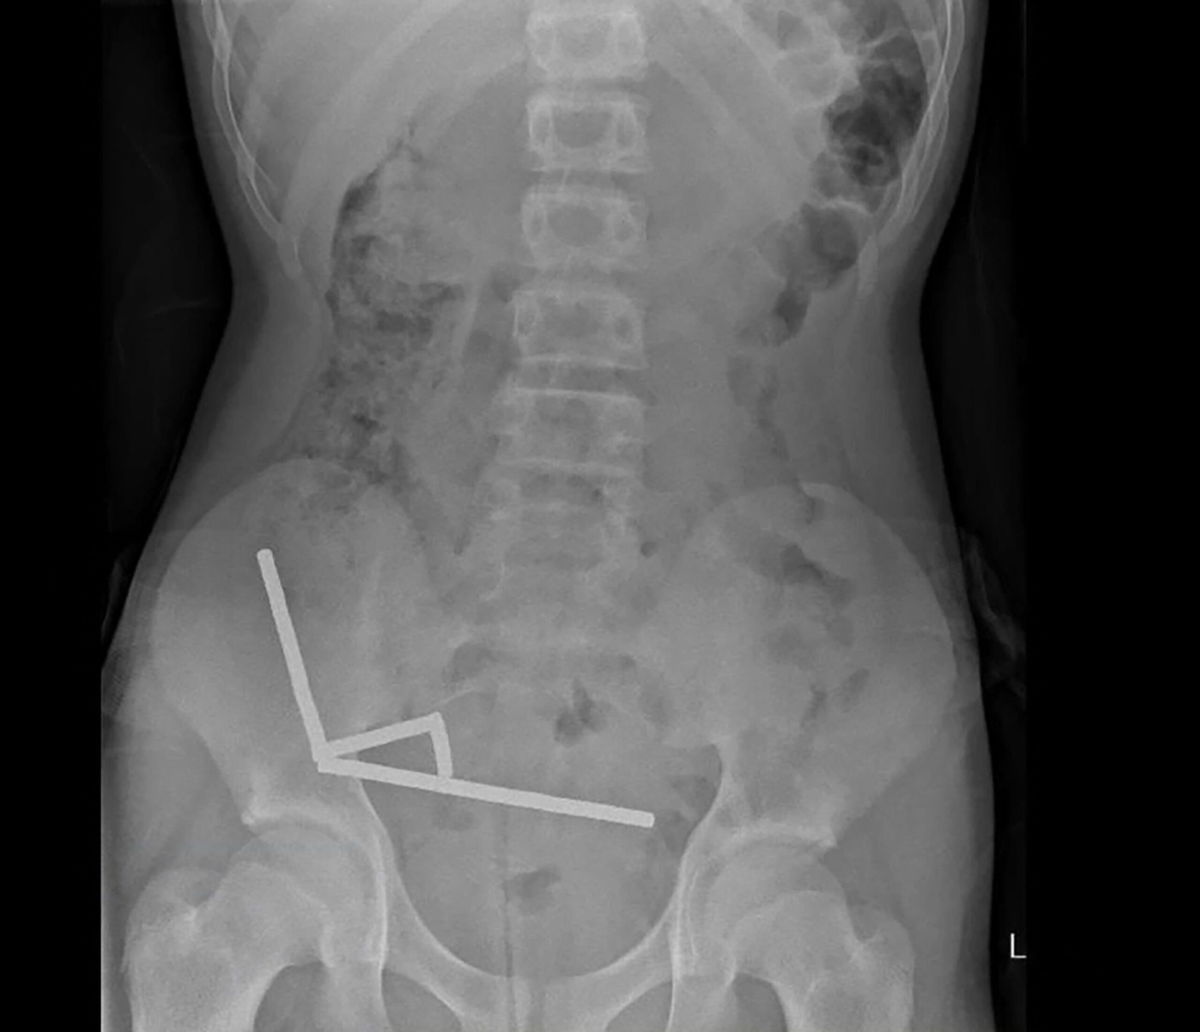

This undated handout released on Friday from the New Zealand Medical Journal (NZMJ) shows an x-ray image of pieces of high-power magnets clumped up in the intestines of a New Zealand teenager in Tauranga.

Scans revealed the magnets had clustered into four chains in the lower-right side of his abdomen, pulling together different sections of his bowel with their magnetic force, the report said, noting some imagery was distorted by the magnets. Doctors then proceeded with exploratory surgery.